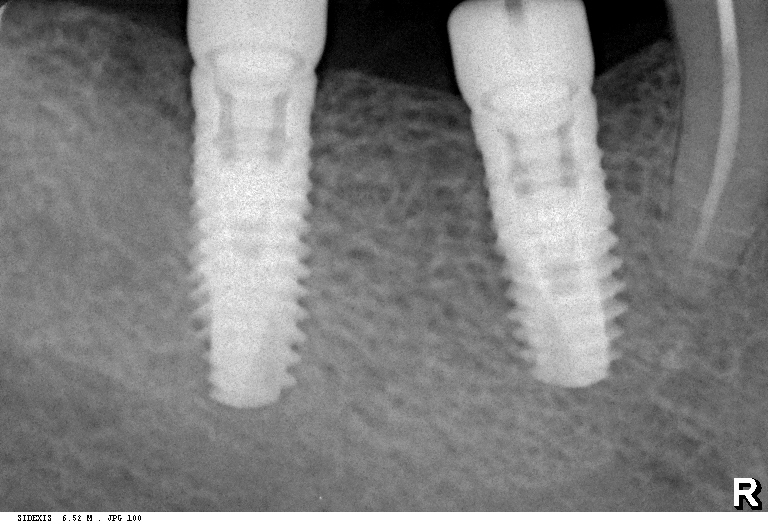

В 2025 году мы внедрили две новые для себя имплантационные системы компании Dentsply Sirona Implants: Astra Tech EV и PrimeTaper EV. В сравнении с уже имеющимися, эти системы уже адаптированы к т. н. «цифровому протоколу», имеют все необходимые компоненты для работы по современным методикам протезирования.

Мы работаем с новыми имплантами уже полгода, накопили приличный опыт их использования, дотошно их изучили и уверенно можем утверждать, что получили в свои руки мощный инструмент стоматологической реабилитации. Поэтому в следующем году тебя ждет не одна и не две публикации о новых имплантационных системах Dentsply Sirona Implants. Они появятся сразу, как мы получим внятные долгосрочные результаты их применения.